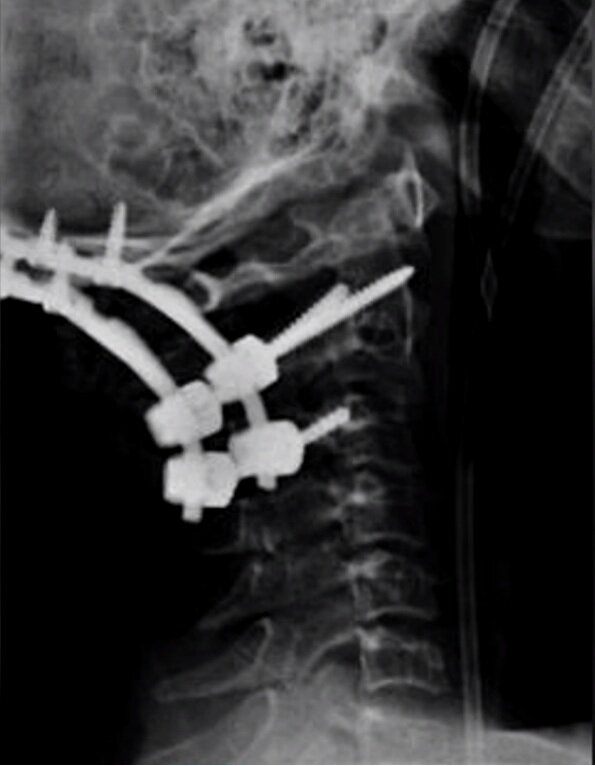

Крис Стюарт.

Когда ему было 12 лет, он мчался на своем гоночном карте и врезался в барьер на скорости 60 километров в час. В аварии он получил травму, которая называется внутренним обезглавливанием: череп Криса был отделен от его позвоночника. Ему давали 10-процентный шанс на выживание, а врачи утверждали, что он должен был умереть мгновенно. Удивительно, что в 2006 году они закрепили его череп, использовав металлические пластины и костные трансплантаты, и уже через несколько лет он снова начал участвовать в гонках.